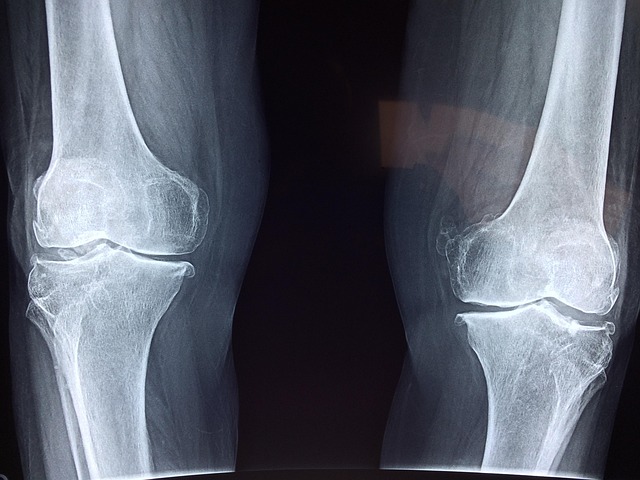

병원에 가야 하는 기준은 언제일까?

무릎 통증이 있다고 해서 모두 병원 치료가 필요한 것은 아닙니다.

하지만 다음과 같은 경우라면 전문 진료를 한 번쯤 받아보는 것이 좋습니다.

통증이 2주 이상 반복될 때

무릎을 움직일 때 소리가 자주 날 때

통증 때문에 보행이 불편해질 때

무릎이 자주 붓거나 열감이 느껴질 때

특히 통증이 점점 잦아지거나 범위가 넓어진다면

단순 근육 피로가 아니라 관절 구조 변화가 시작됐을 가능성도 있습니다.